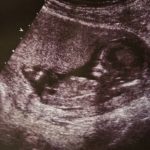

Bebeğin ultrason fotoğraflarından her şey belliydi. Uzman doktorun görüşüne göre bebeğin doğduktan sonra yaşama şansı %10’du. En iyi ihtimalle çocuk yaşasa bile hayatı boyunca beyninden tedavi görmesi gerekecekti.